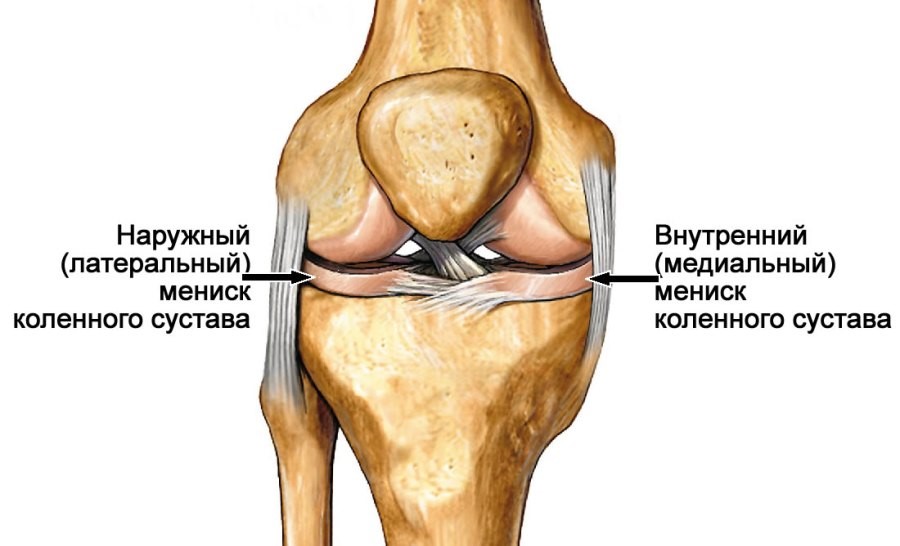

Рисунки Суставов: Анатомические Иллюстрации